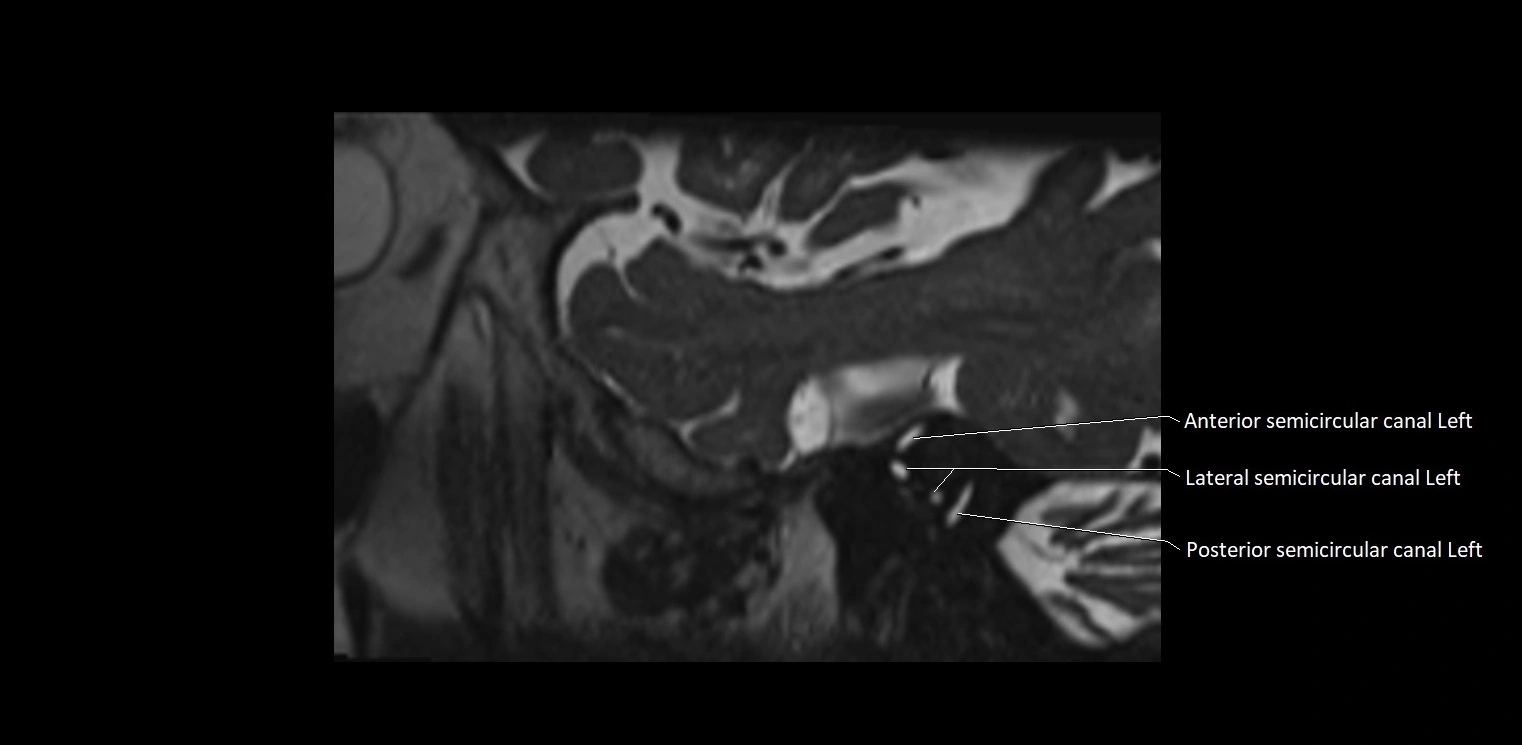

MRI Appearance

• The abducens nerve is a small, thin, linear structure

• Best visualized on high-resolution T2-weighted 3D MRI sequences (e.g., FIESTA or CISS)

• Seen as a hypointense (dark) line running from the brainstem at the pontomedullary junction, traversing the prepontine cistern, and entering Dorello’s canal under the petrosphenoidal ligament, then into the cavernous sinus, and finally the orbit

• May be challenging to visualize in standard MRI due to its small size

• Pathology may be inferred by absence, displacement, or enhancement of the nerve